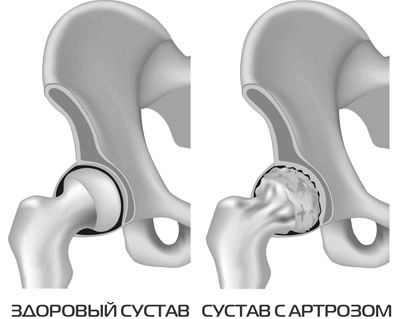

Чому погіршується стан при надлишкових навантаженнях на уражені суглоби, зрозуміти нескладно. В одній з книг Євдокименко порівнює хрящ з підшипниковий механізмом. Зруйнований артрозом суглоб перестає бути округлим, «підшипник» покривається мікротріщинами і заусенцами, а мастило стає густою і в'язкою.

Якщо запускати такий механізм, чи стане він від великих навантажень знову гладким? Або, навпаки, він швидше зруйнується? Відповідь очевидна. Саме тому від неправильних вправ з неточно розрахованими навантаженнями і невірної технікою виконання суглоб зруйнується швидше.